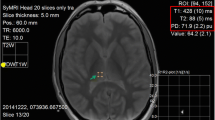

A commercially available post-processing tool (SyMRI Autopsy, SyntheticMR, Linköping, Sweden) [22] was used to measure the T1 and T2 relaxation times and PD by placing five ROIs in organs (myocardium, liver, spleen) and tissues (subcutaneous fat and pectoralis muscle) covered on cardiac short axis images (Fig. 2). T1 and T2 relaxation times in milliseconds (ms) as well as the PD (%) were plotted in a 3D plot using the ThreeDifyExcelGrapher add-in for Microsoft Excel® to investigate clustering and separation of organs and tissues. Two-way analysis of variance (ANOVA) was carried out to look for significant differences of quantitative T1, T2 and PD values between all organs/tissues. The null hypothesis was rejected when the p value was less than 0.05.